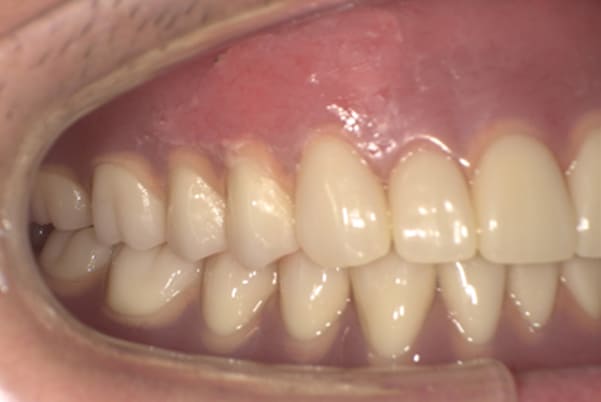

治療前後の口元の比較

こちらは、口を少し開いた時の治療前と治療後の

口元です。

正面から見た時にクラスプが目立たないように、

歯ぐきになじむ素材にて入れ歯を製作し、痛くなく自然に馴染み快適に生活を送れるようになりました。